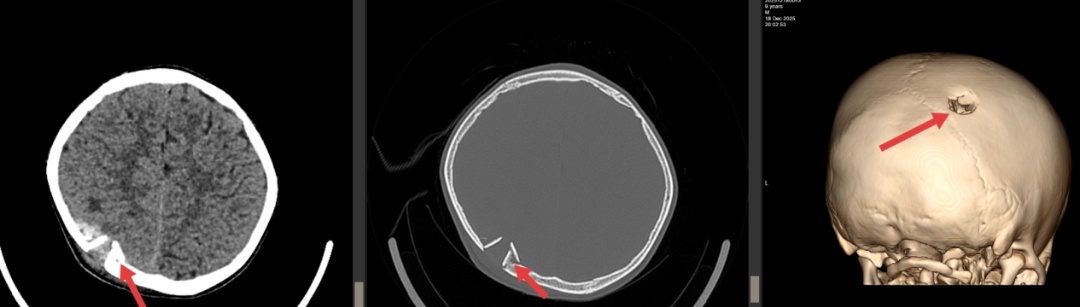

小明被紧急送往广西医大开元埌东医院。闫学强与住院医师张景炎医生接诊后立即安排影像检查,结果显示小明右顶骨凹陷性骨折,骨折碎片刺破硬脑膜造成脑组织挫伤和硬膜外血肿,情况十分危急。

术前CT检查。

“患儿送来时出现外伤性癫痫症状,颅骨碎片已嵌入脑组织,必须立即手术。”闫学强说。由闫学强主刀、张景炎担任助手的手术团队迅速启动绿色通道,当晚即为小明实施了开颅手术。

手术历时3个小时,医生成功取出了嵌入脑组织的颅骨碎片、清除血肿,并修复受损的硬脑膜。“手术中我们发现部分颅骨碎片已经刺入脑组织约5毫米,非常接近运动功能区,如果延误治疗可能导致永久性肢体功能障碍。”闫学强回忆道。手术顺利完成,术后癫痫未再发作,小明意识逐渐恢复,语言和肢体活动正常。复查CT显示颅骨形态良好,脑组织无新发出血,小明顺利康复出院。